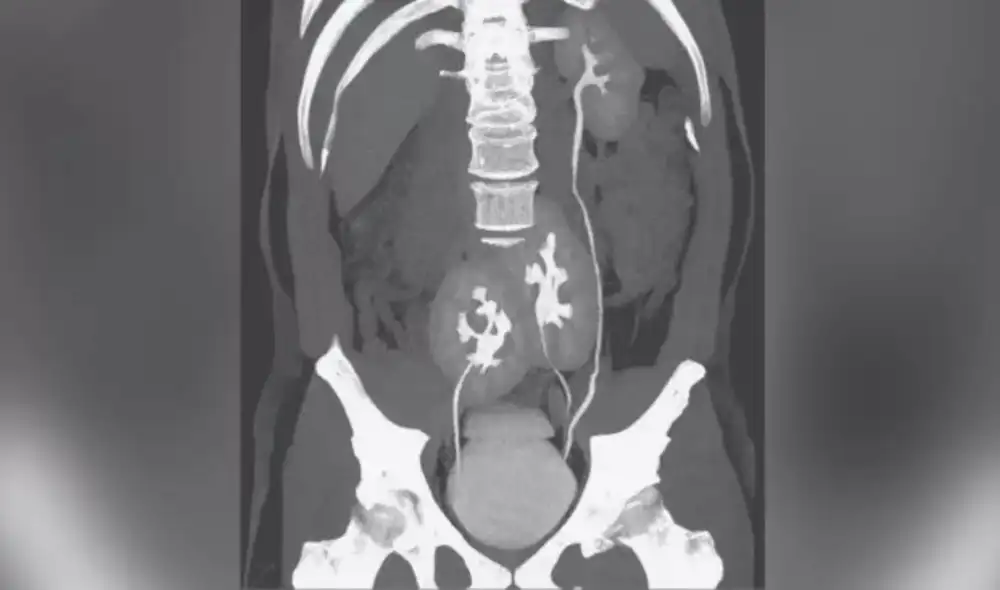

Este fue el caso de un hombre de 38 años en Brasil que, en 2020, fue al médico por un dolor lumbar. Sin embargo, tras una tomografía computarizada, él descubrió que tenía esta extraña condición.

El tercer órgano se encontraba fusionado con el riñón del extremo derecho, cerca de la pelvis, indicó un artículo de la revista The New England Journal of Medicine (NEJM).